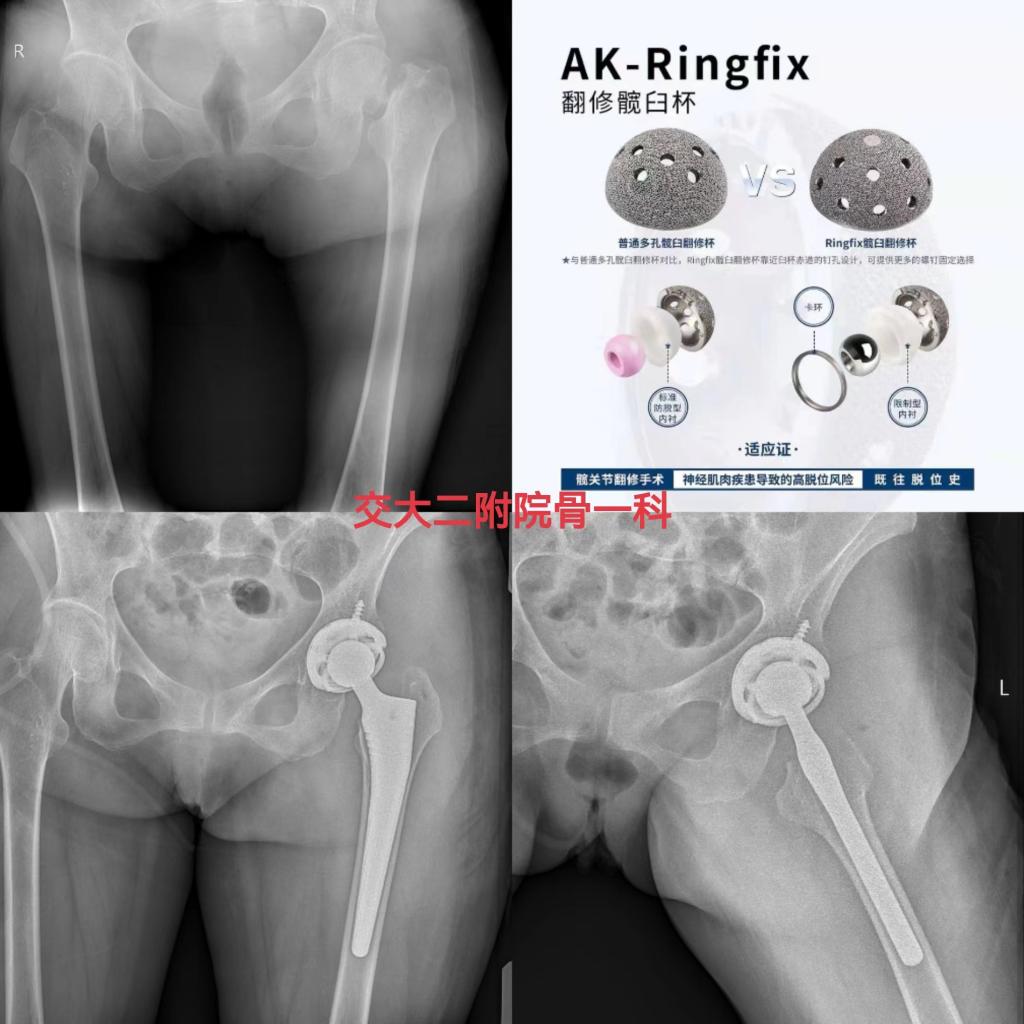

近期,骨一科收治多例需要进行髋关节复杂初次置换和翻修的患者,且病情复杂,手术难度大,党晓谦主任和时志斌副主任高度重视,组织全科对患者病情进行讨论分析,借助3D打印技术和计算机模拟手术技术,最终确定手术方案,在党晓谦主任的主刀下,手术顺利完成,术后患者恢复良好,均已顺利出院康复。

一位患者摔伤后左髋部疼痛活动受限3天,诊断为左侧股骨颈骨折(Garden Ⅳ型),骨质疏松症,癫痫,完善相关检查排除手术禁忌后,由时志斌副主任主刀完成我院首例左髋关节置换术(AK-Ringfix限制性假体),术后恢复良好,已顺利出院。